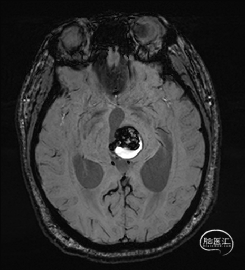

术前MRI检查

术前DTI检查

术前MRI检查提示左侧丘脑中脑海绵状血管瘤并卒中,梗阻性脑积水;

根据MRI及DTI显示,只有在丘脑与上丘之间的点(dot)进入病变才可能在切除病变时最大程度保护神经功能,由于上述原因,该“点”在术中显露极其困难,虽有导航指引,电生理监测的条件下,对术者的耐心、技术、经验及体能依然是极大的挑战;

术前详细的磁共振检查,包括平扫增强,SWI及DTI,可以规划出手术最适宜的路径及切入点;